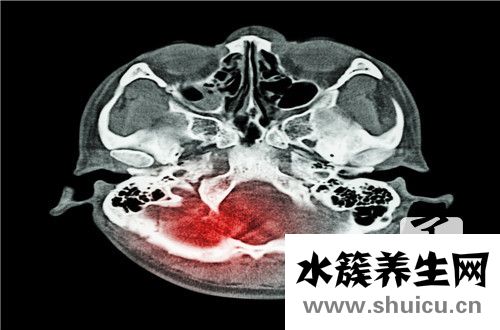

慢性硬膜下血腫是一個常見的腦部問題。這種問題的發(fā)生對病人來說是比較嚴重的。如果治療不及時或治療方法不正確,很可能導(dǎo)致患者出現(xiàn)癡呆、偏癱等癥狀,甚至直接導(dǎo)致患者死亡。因此,當(dāng)出現(xiàn)慢性硬膜下血腫時,必須及時進行治療!

慢性硬膜下血腫是指